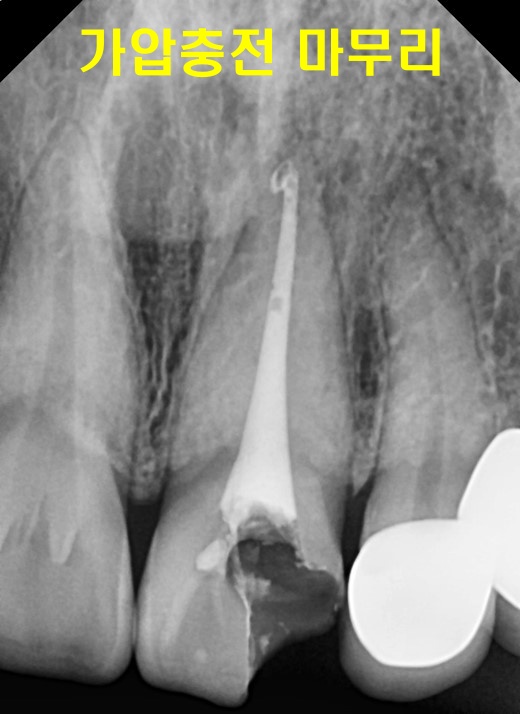

그렇게 치아 뿌리부터 잘 채워줬다면,

치아 머리(치관) 에는 레진이라는 재료로

채워주는 “코어”를 해 줍니다.

레진 코어를 한 상태로 보여집니다.

이후 크라운을 씌워야 할 것으로 예상됩니다.